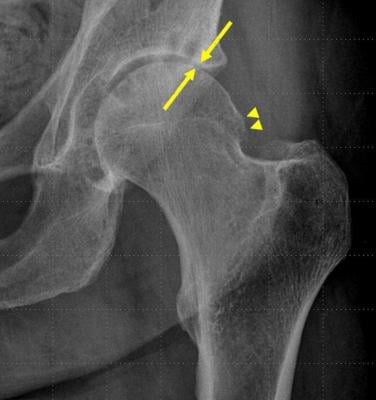

58-year-old woman with left hip pain. X-ray from one month prior to the steroid/anesthetic injection demonstrates moderate joint space narrowing (arrows) and bony proliferation (arrowheads).

"Changes due to osteoarthritis, such as narrowing in the space between joints and the development of bony proliferations, typically develop slowly over time," said Connie Y. Chang, M.D., radiologist at Massachusetts General Hospital and assistant professor of radiology at Harvard Medical School in Boston. "When reading follow-up radiographs of patients who had received a hip injection, we noticed changes had developed rapidly in some patients."